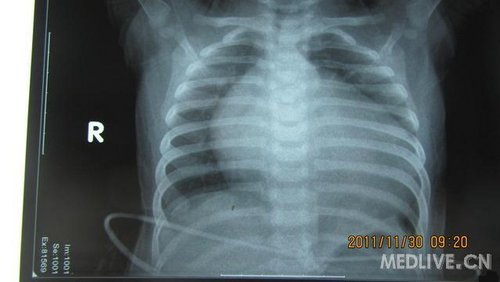

患儿,女,6月,足月剖腹产,出生后家长发现喘憋,未重视。现症状加重,不能喂食而就诊!

片子列出,急盼高手指点,不知生存几率有几分?